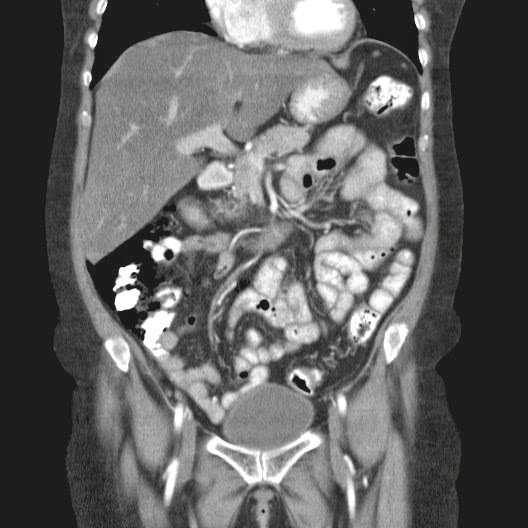

Caso Interesante #4

Adulto masculino, 1 semana de fiebre y malestar general.

¿Dónde esta ubicado el hallazgo?